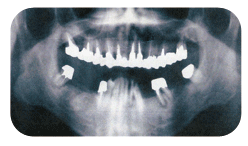

インプラント

・顎の骨の量や質を検査するためレントゲン撮

影、またはCT撮影を行います。